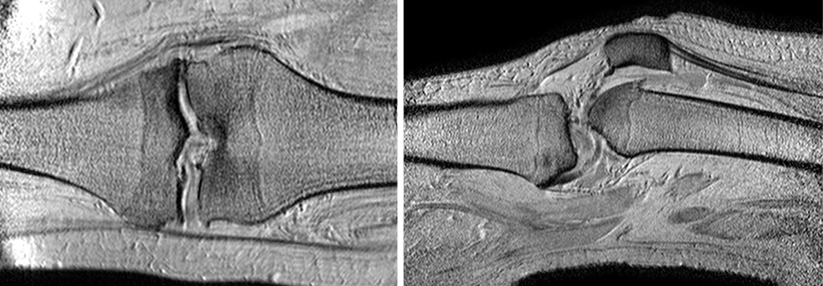

Die bisherigen Daten sprechen dafür, dass ein Krafttraining patellofemorale Schmerzen lindert. Unklar war jedoch, ob eher die Muskulatur von Knie oder Hüfte beübt werden sollte. Auf der Suche nach einer Antwort starteten dänische Wissenschaftler eine kontrollierte Studie.

200 Teilnehmer im mittleren Alter von 27 Jahren wurden randomisiert, mehrheitlich Frauen. Die eine Hälfte trainierte den Quadrizeps, bei der anderen stand die Hüftmuskulatur im Fokus. Primär gemessen wurde die Veränderung in der Anterior Knee Pain Scale (AKPS) innerhalb eines Zeitraums von zwölf Wochen.